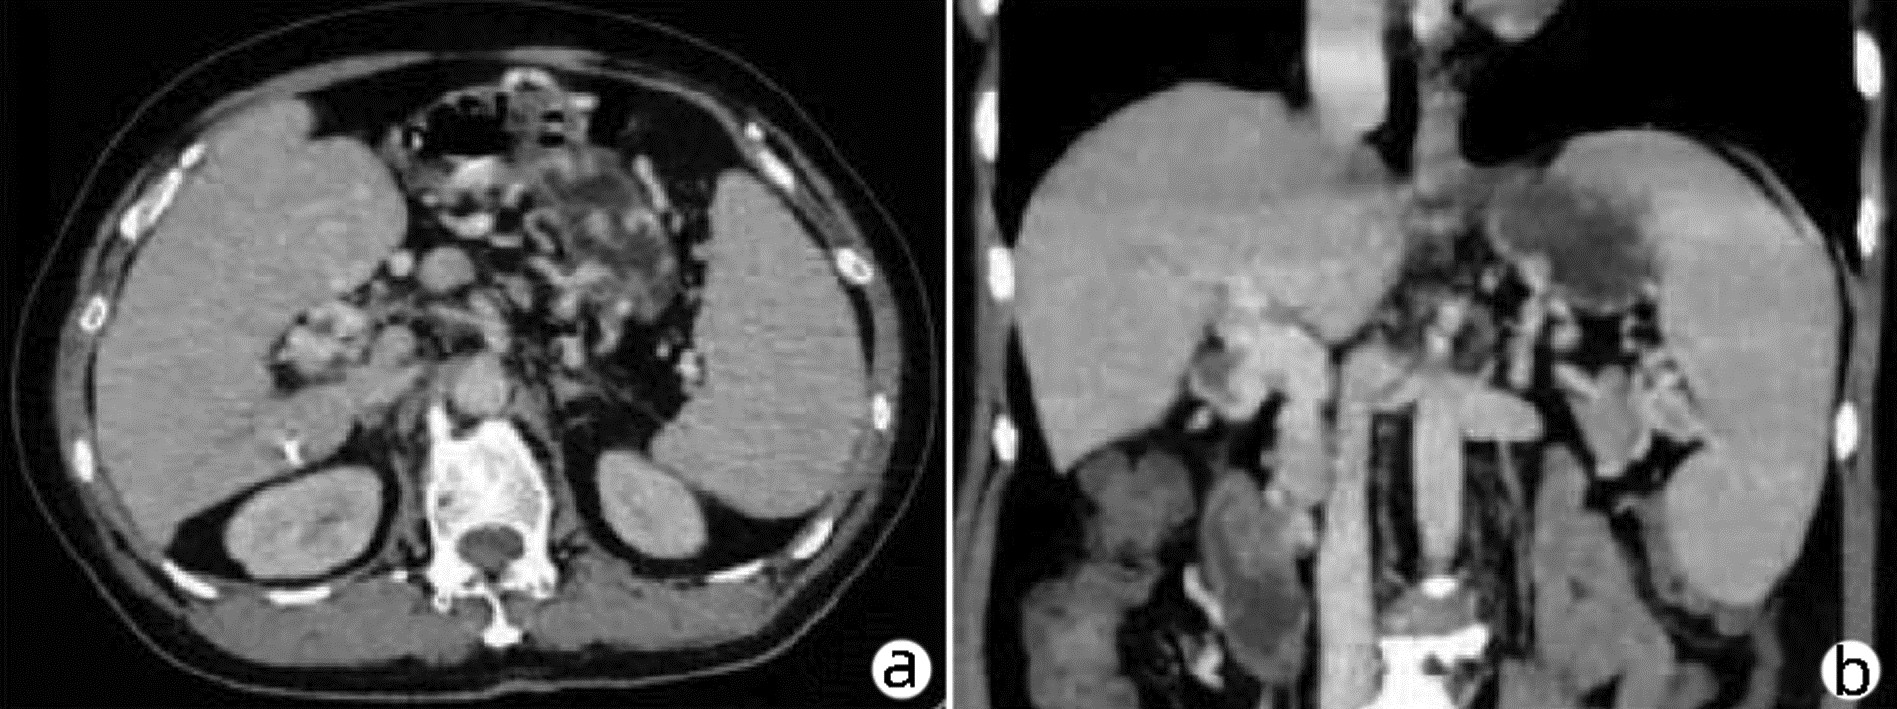

Congenital left hepatic deficiency with hepatocellular carcinoma: A case report

Hailin WANG, Jingdong LI, Guo WU

2023, 39(6): 1408-1410. DOI: 10.3969/j.issn.1001-5256.2023.06.023

Abstract(853) HTML (199) PDF (2003KB)(65)